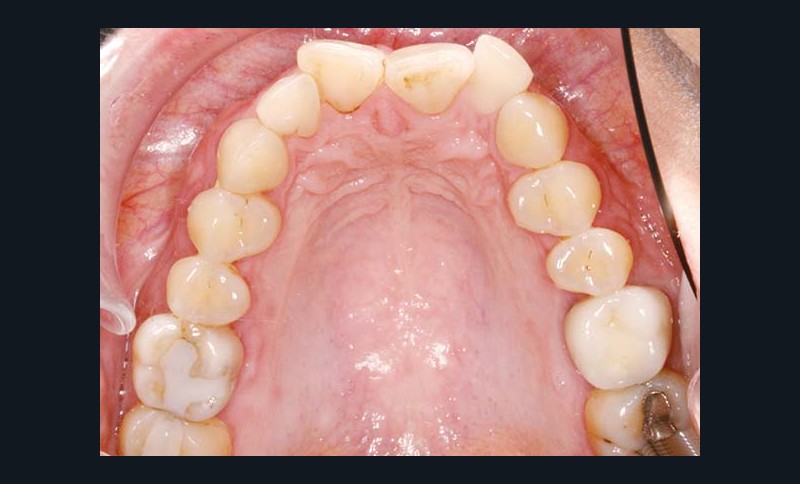

La patiente âgée de 40 ans présente une classe II bilatérale associée à une dysharmonie dento-maxillaire modérée et à une supraclusion de 50 %.

Sur le plan squelettique, les bases osseuses sont en classe II (ANB = 5°) et en bi-rétroposition (SNA = 78°, SNB = 73°). Au niveau des tissus mous, la patiente montre un profil labial concave, une rétrogénie et une distance cervico-mentonnière courte. Les tissus sous-mentonniers sont affaissés et l’angle naso-labial est de 90° (fig. 1 à 9).